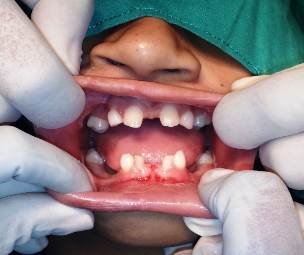

En la anamnesis no se refieren otras alteraciones familiares o genéticas y en el examen clínico se observa la falta de varios dientes temporales y permanentes, sin signos visuales de posible brote dental, por lo que se indica radiografía panorámica. Frenillo superior e inferior anormal.

La paciente recibió tratamiento quirúrgico en Parodoncia, frenectomía superior e inferior (Figura 2).